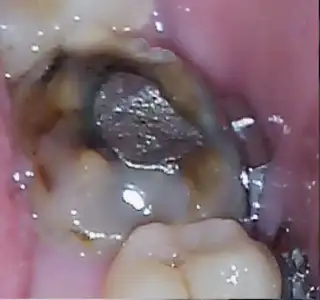

kök dişim kanal yapılmış bir dişti baya çürüdü rengi değişti gri gibi bişey oldu fakülte ortodontistin gerek duymadığı yada izin vermediği sürece dolgu kanal vb ilgilenemeyiz diyo bu sefer ortodontisime gidiyorum bu diş iyi yok işte dahada kazıyıp incelticekler dişini diyip başından savuşturuyo

internetten araştırdım bu sonradan olan renk değişimleri dişin grileşmesi gücünü kaybettiğini gösterir yazıyo hadi onu geçtim bariz çürüme var yarın bi gün iltihap yapıcak diğer dişleride çürüticek diye korkuyorum yoksa kalsın durduğu yerde sizce ne yapmalyım

internetten araştırdım bu sonradan olan renk değişimleri dişin grileşmesi gücünü kaybettiğini gösterir yazıyo hadi onu geçtim bariz çürüme var yarın bi gün iltihap yapıcak diğer dişleride çürüticek diye korkuyorum yoksa kalsın durduğu yerde sizce ne yapmalyım (galiba açık olmadı fakülteler bir iki yada üç ay gibi sürelerde solgu kanal vb için rabdevu veriyo eğer ortodontistinin isteği ve izni ile olusa yarınına randevu alabiliyosun ama ortodontis gerek yok diyo bu yüzden 2 3 ay beklicem yada ağrılarım şiddetlenmeden dişimi çektiricem aynı durumu yaşayanlar varsa yadımcı olabilirlermi acabasizinde diş teli taktırdıktan sonra dolgulu ve kanallı dişlerinizde renk değişmesi dişlerinizde grileşme kahverengileşme oldumu doktora söylüyorum bişey olmaz yok işte tekrar işlem için dişini biraz daha kazıyıp incelticekler idare ettiği kadar öle kalsın diyip duruyo özellikle alttaki dişim bildiğiniz koyu gri oldu